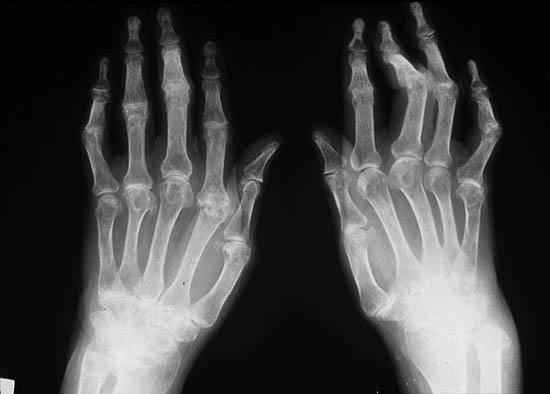

Las partes de nuestro cuerpo que más ataca esta enfermedad son los tobillos, los codos, y también los dedos de las manos así también como los dedos de los pies, tanto en mujeres como en los hombres y su aparición es más que todo en la edad comprendida entre los 30 y los 50 años en ambos sexos, se puede empezar a manifestar en la piel o también se puede manifestar en nuestras articulaciones

Mucho dolor y mucha inflamación en nuestros codos, muñecas, rodillas, y en los dedos de las manos así como los dedos de nuestras manos, los dedos toman la apariencia como si fueran una salchicha tanto por lo inflamado como por el color que adquieren, también aparecen fuertes dolores en la espalda así como también dolores en los glúteos y en el cuello, la piel toma una apariencia de tener escamas las que se desprenden dando ya están muy resecas